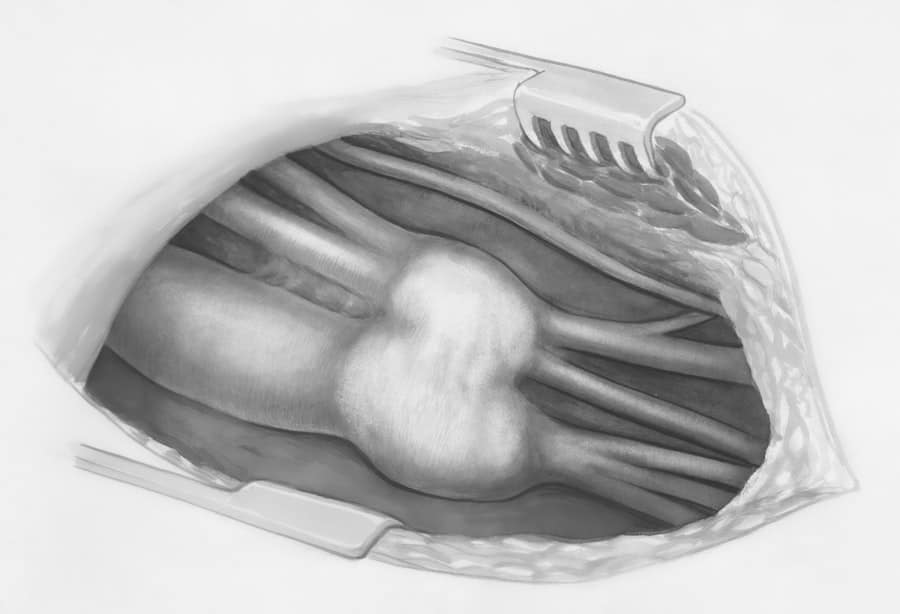

Traditional Open Rhinoplasty

This technique involves a small incision made on the columella, the strip of skin separating the nostrils.

- Advantages: The open approach provides the surgeon with excellent visibility of the nasal structures, allowing for precise modifications. This is often preferred for complex cases, revision rhinoplasties, or when significant structural changes are required.

- Disadvantages: The external incision leaves a small, usually imperceptible scar. Recovery may be slightly longer for some individuals compared to the closed technique.

- Cost Factor: Due to the enhanced visibility and precision, open rhinoplasty can sometimes be more time-consuming and, therefore, may carry a slightly higher fee than closed rhinoplasty for less complex cases.